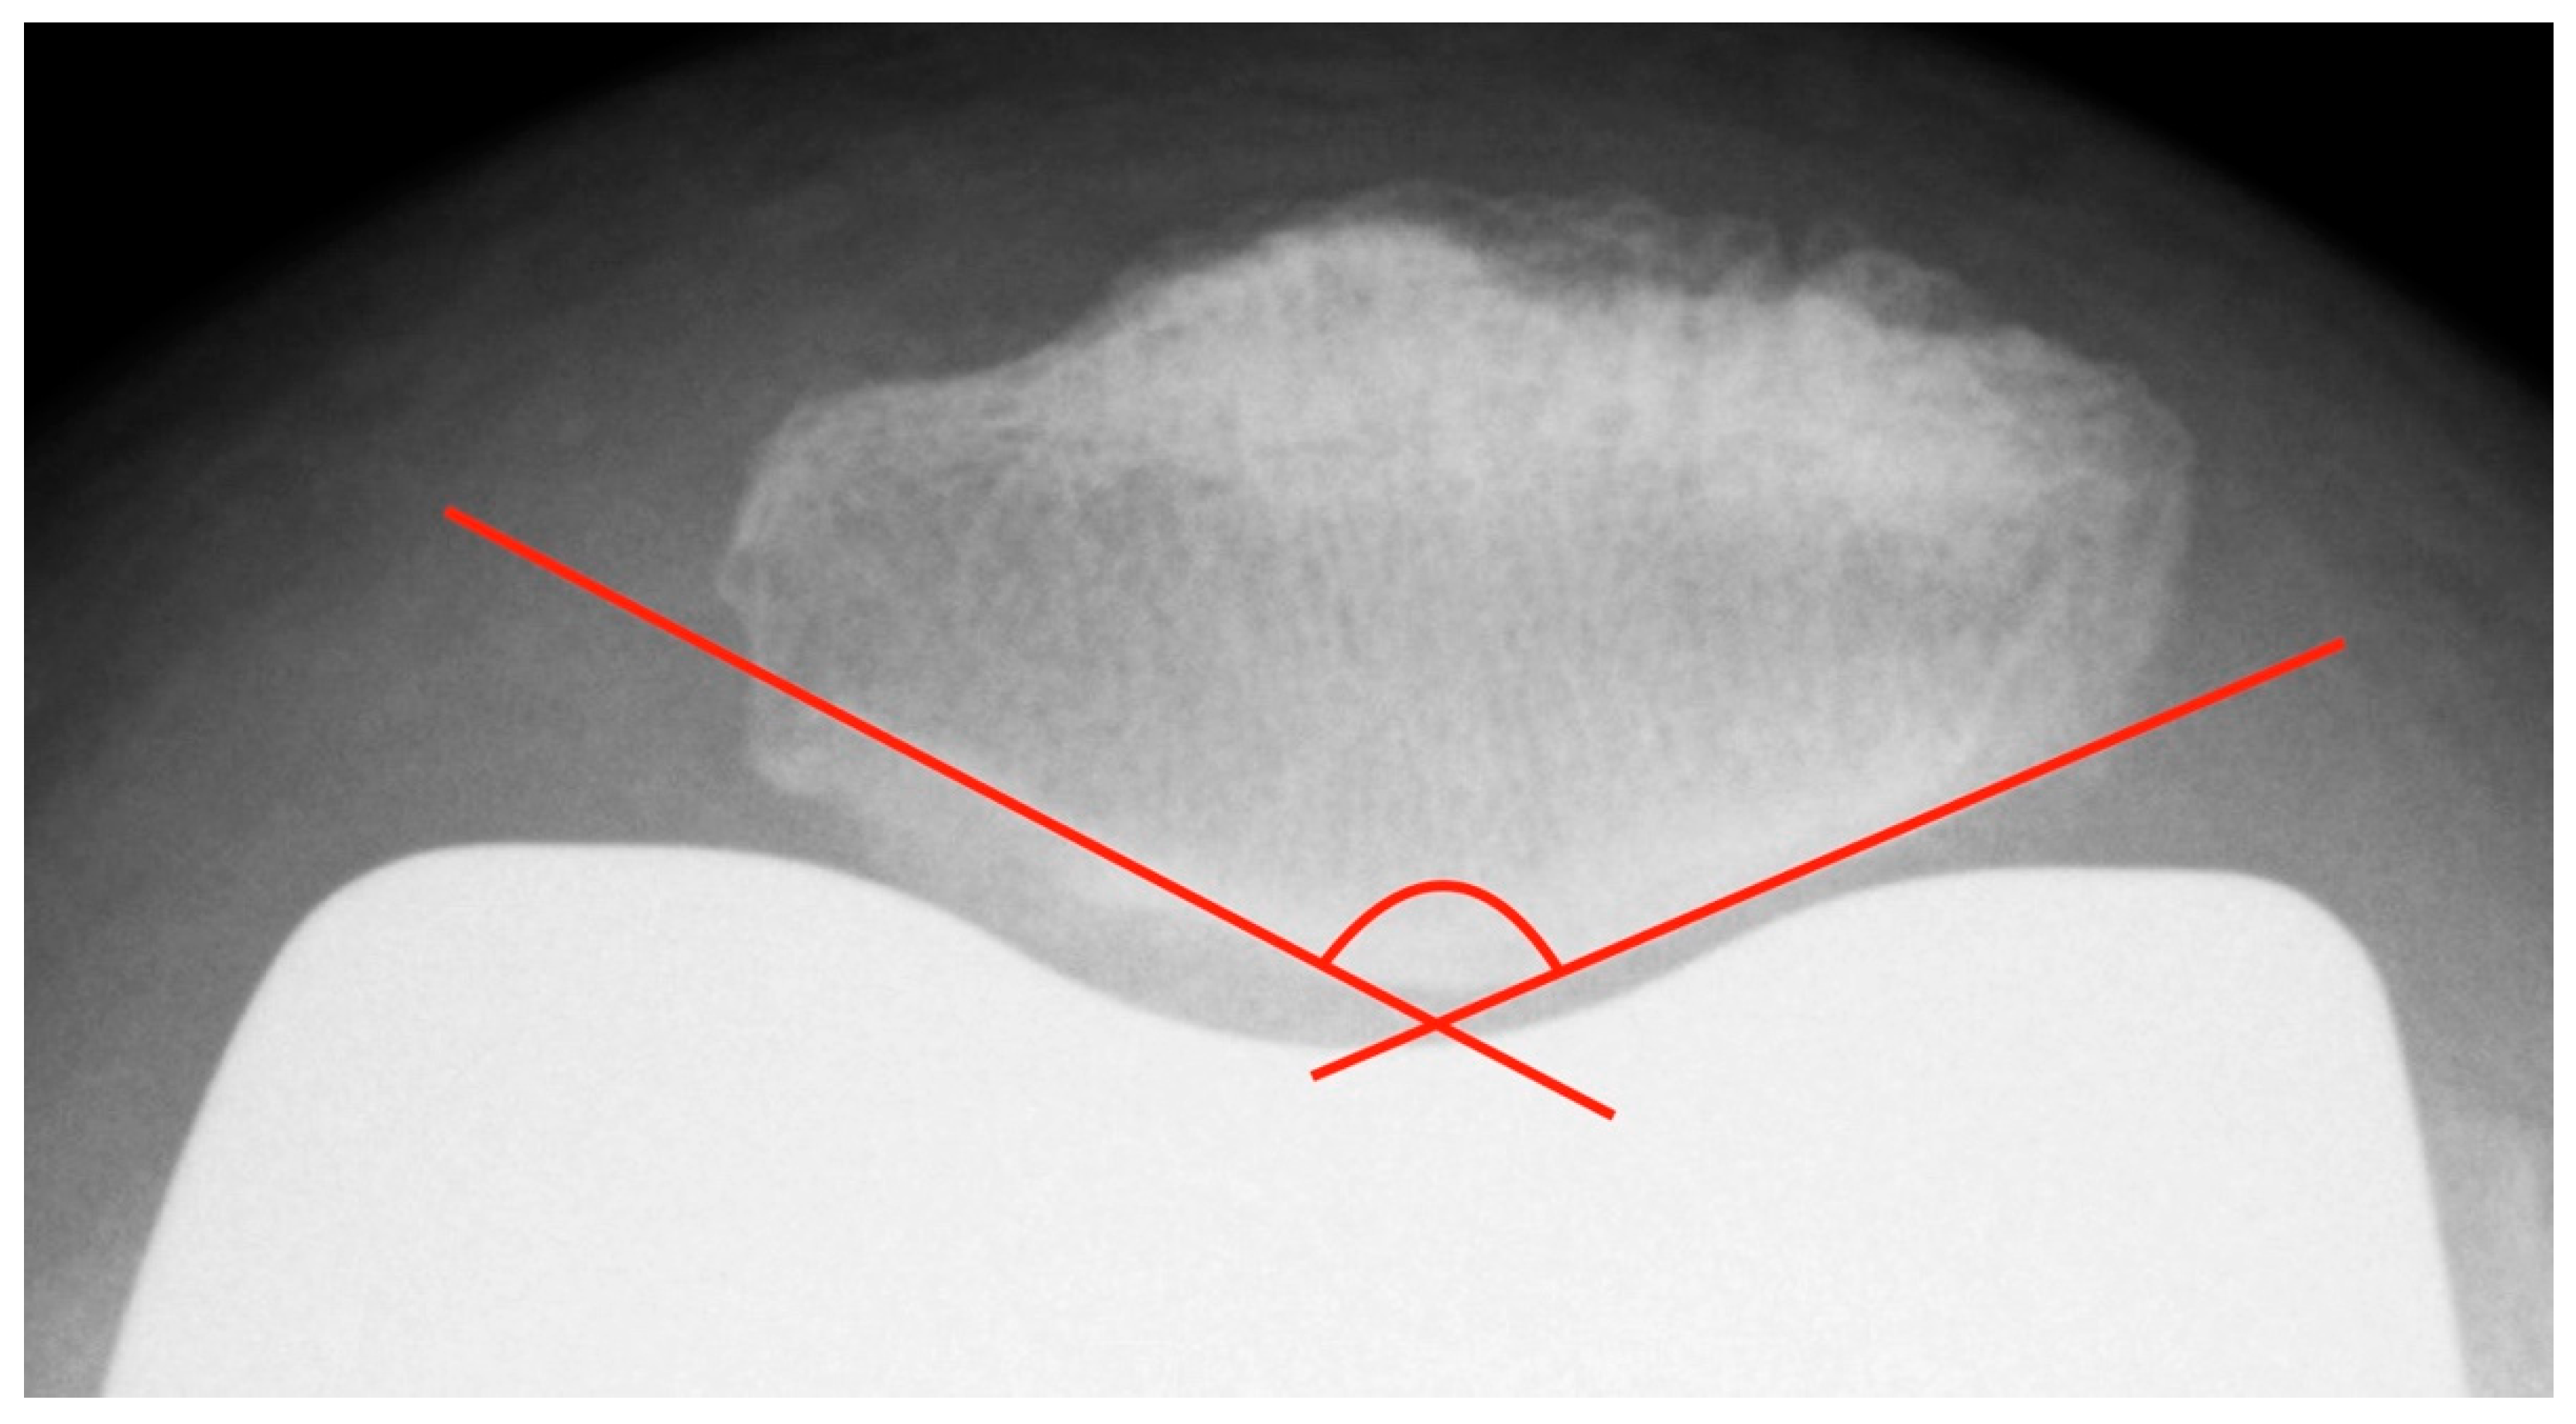

2.3.4. Patellar Morphology

To ascertain the patellar shape type and to distinguish patellar euplasia from dysplastic variants, the patellar joint surface angle (facet angle) described by Christiani was measured. This angle is formed by the patella ridge and each the medial and lateral joint facet [25] (see Figure 6). On axial radiographs in 60° knee flexion, this angle should be between 120° and 139°. Values < 115° and ≥ 145° are considered as dysplastic [26].

Figure 6.

Measurement of the patellar facet angle with the method of Christiani. Additionally, the image shows an example of possible difficulties in determination of patellar facet tangent, in this case due to bony superimposition at the medial facet.